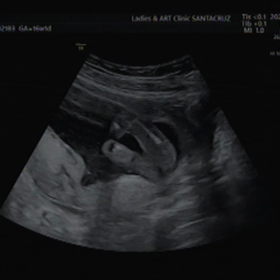

• 転院前の最後26週目の妊婦検診の画像

転院前の最後26週目の妊婦検診